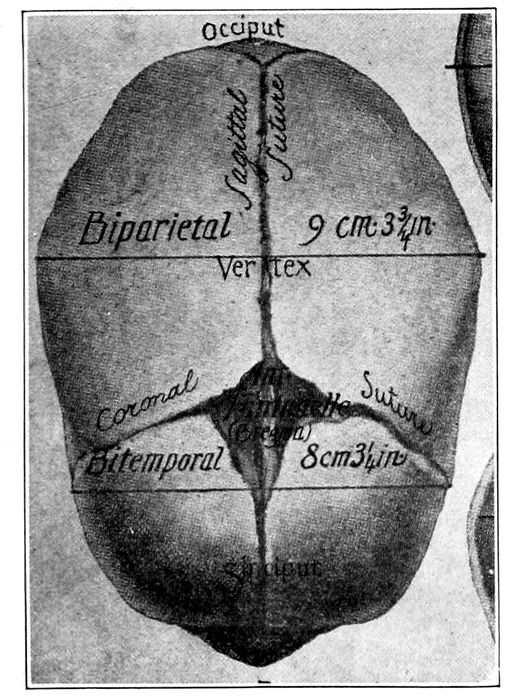

Fig. 22 A.—Child’s head at term (from side), showing diameter. (American Text Book.)

Fig. 22 B.—The child’s head at term (from above), showing diameters and fontanelles. (American Text Book.)

In front, the two coronary sutures meet the frontal

and sagittal sutures to produce a kite-shaped figure,

called the large or anterior fontanelle, or the bregma.

Behind, the lambdoidal suture meets the sagittal suture

to form the small or posterior fontanelle.

The large fontanelle is made up of four bones and

four angles; the small, of three bones and three angles,

and are usually easy to differentiate. Furthermore,

the difference between these fontanelles is of great importance

in labor, since by it the observer is enabled to

determine the position of the head. In America, the

shape of the head is that of an ovoid with the long

diameter anteroposterior (Dolico-cephalic). Thus it

happens that when the head is completely flexed, the

smallest diameters are presented for delivery.

The important diameters of the head, with their measurements

and names, are as follows:

Nape of neck to center of bregma, 9.5 cm.—Suboccipito-bregmatic

diameter. Occipital protuberance to root

of nose, 11.25 cm.—Occipito-frontal diameter. Between

the eminences of parietal bones, 9.25 cm.—Biparietal

diameter. Between anterior ends of coronal sutures, 8

cm.—Bitemporal diameter.

The smallest circumference is that of the suboccipito-bregmatic

plane, which comes into relation with

the brim of the pelvis when the flexion of the head is

complete. It measures 27.5 centimeters.